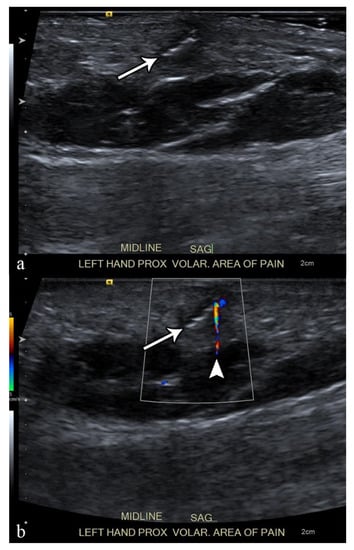

2.4. Abscess

- Bureau, N.J.; Chhem, R.K.; Cardinal, E. Musculoskeletal infections: US manifestations. Radiographics 1999, 19, 1585–1592. [Google Scholar] [CrossRef] [PubMed]

- Craig, J.G. Infection: Ultrasound-guided procedures. Radiol. Clin. N. Am. 1999, 37, 669–678. [Google Scholar] [CrossRef]

- Loyer, E.M.; Kaur, H.; David, C.L.; DuBrow, R.; Eftekhari, F.M. Importance of dynamic assessment of the soft tissues in the sonographic diagnosis of echogenic superficial abscesses. J. Ultrasound Med. 1995, 14, 669–671. [Google Scholar] [CrossRef] [PubMed]

- Davae, K.C.; Sofka, C.M.; DiCarlo, E.; Adler, R.S. Value of power doppler imaging and the hypoechoic halo in the sonographic detection of foreign bodies: Correlation with histopathologic findings. J. Ultrasound Med. 2003, 22, 1309–1313; quiz 1314–1316. [Google Scholar] [CrossRef] [PubMed]